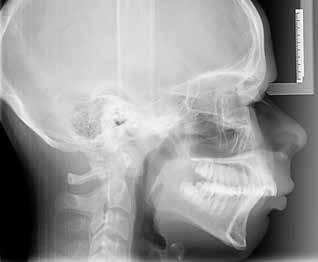

INDRE VÆKSTFORSTYRRELSER I DEN DENTOALVEOLÆRE OG BASALE KÆBERELATION kan almindeligvis kompenseres og korrigeres ved ortodonti og/eller vækstadapterende behandling (1). Imidlertid nødvendiggør ekstreme vækstforstyrrelser i den dentoalveolære og basale kæberelation oftest ortodontisk-kirurgisk behandling involverende forudgående ortodontisk nivellering af tandbuerne og efterfølgende kirurgisk korrektion af de basale kæberelationer ved en Le Fort I-osteotomi og/eller bilateral sagittal splitosteotomi (BSSO) (2). Manglende korrektiv behandling af vækstforstyrrelser i den dentoalveolære og basale kæberelation kan medføre tygge- og bidfunktionelle gener, malokklusion, tvangsføring af mandiblen, trangstilling, psykosociale problemer og uhensigtsmæssigt slid af tænderne (3). Sundhedsstyrelsens specialevejledning har derfor opstillet vejledende kriterier for tilbuddet om kirurgisk korrektion af medfødte og erhvervede kæbeanomalier, når vækstforstyrrelserne i den dentoalveolære og basale kæberelation ikke kan korrigeres ved konventionel ortodontisk behandling alene (4). Disse visitationsretningslinjer kan findes på Dansk Selskab for Oral og Maksillofacial Kirurgis og Foreningen af Specialtandlæger i Ortodontis hjemmesider.

Fig. 1. Klinisk undersøgelse visende et stort horisontalt maksillært overbid kombineret med et dybt bid og bilateralt saksbid på molarerne og præmolarerne.

Fig. 1. Clinical examination revealed a large horizontal maxillary overbite combined with a deep bite and bilateral scissor bite on the molars and premolars.

Betragtelige transverselle okklusionsafvigelser i maksillen behandles almindeligvis med vækstadapterende ortodontisk behandling før begyndelse af vækstspurten, mens kirurgisk korrektion ved en sektioneret Le Fort I-osteotomi eller kirurgisk assisteret ganeekspansion oftest er nødvendig efter afsluttet vækst (3). Transverselle okklusionsafvigelser i mandiblen kan ikke korrigeres ved vækstadapterende ortodontisk behandling som følge af afsluttet vækst i sutura symphysis menti før etårsalderen, hvorfor betragtelige transverselle okklusionsafvigelser oftest korrigeres ved en udvidelse eller komprimering af maksillen (5). Imidlertid er kirurgisk korrektion af betragtelige transverselle okklusionsafvigelser ved en sektioneret Le Fort Iosteotomi eller kirurgisk assisteret ganeekspansion forbundet med stor tendens til recidiv (3), hvorfor transversel udvidelse af mandiblen kan være nødvendig for at mindske recidivtendensen.

Betragtelige transverselle okklusionsafvigelser i den underudviklede mandibel kendetegnes ved en V-formet tandbue, unieller bilateralt saksbid, oral inklinering af molarerne og præmolarerne samt trangstilling i underkæbefronten (6). Mindre transverselle okklusionsafvigelser i mandiblen kan oftest korrigeres ved hjælp af ortodonti alene, mens større transverselle okklusionsafvigelser eventuelt i kombination med andre vækstforstyrrelser i den dentoalveolære og basale kæberelation oftest behandles ved kirurgisk korrektion involverende mandibulær midtlinjeosteotomi eller mandibulær midtlinjedistraktionsosteogenese (MMDO) (6).

Mandibulær midtlinjeosteotomi anvendes almindeligvis ved moderate transverselle okklusionsafvigelser og kan eventuelt kombineres med en bilateral sagittal splitosteotomi, mens mandibulær midtlinjedistraktionsosteogenese udelukkende anvendes ved ekstreme transverselle okklusionsafvigelser og ikke kan kombineres med andre osteotomier på mandiblen.

I nærværende artikel præsenteres et usædvanligt patienttilfælde med en betragtelig transversel okklusionsafvigelse i mandiblen, som blev korrigeret ved ortodonti og mandibulær

Fig. 2. A-C. Panorama, profilrøntgen og CBCT-optagelse viser overensstemmelse med de kliniske fund visende et stort horisontalt maksillært overbid og bilateralt saksbid i sideregionerne.

Fig. 2. A-C. Panoramic x-ray, profile x-ray, and CBCT-image show agreement with the clinical findings showing a large horizontal maxillary overbite and bilateral scissor bite in the lateral regions.

midtlinjedistraktionsosteogenese, og de forskellige distraktionsapparaturer til korrektion af transverselle okklusionsafvigelser i mandiblen diskuteres.

Fig. 3. A. Gennemgående midtlinjeosteotomi svarende til regio 1-1. B. Distraktionsapparatur monteret og fikseret på hver side af osteotomien. C. Panoramaoptagelse under distraktionsfasen. D. Panoramaoptagelser efter distraktionsfasen er afsluttet. E. Intraoperativt klinisk foto efter fjernelse af distraktionsapparaturet, hvor der ses knogledannelse svarende til den tidligere knoglespalte.

Fig. 3. A. Midline osteotomy corresponding to teeth 31 and 41. B. Distraction appliance mounted and fixed on each side of the osteotomy. C. Panoramic x-ray during the distraction phase. D. Panorama recordings after the distraction phase is finished. E. Intraoperative clinical photo after removal of the distractor showing bone formation corresponding to the previous bone gap.